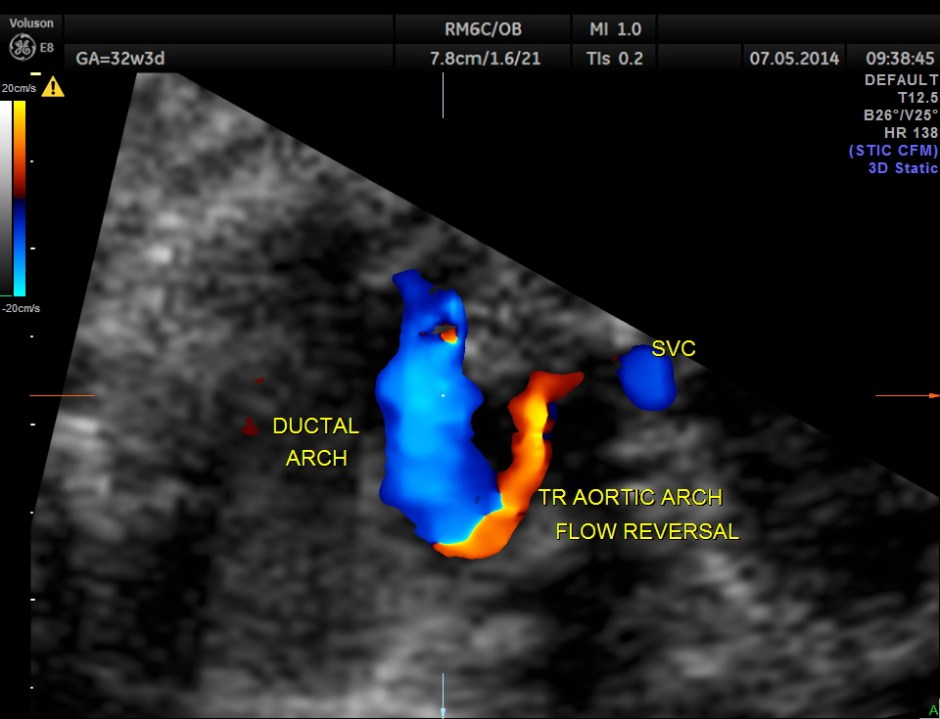

Ductal arch is prominently dilated in comparison to the aortic arch and there appears to be a flow reversal also.

No definitive pulmonary vein draining into the left atrium could be made out . A common transverse vessel was seen beneath the left atrium . The LA & RA were smaller than the RA. Similarly the Aorta and the aortic arch were smaller than the pulmonary artery and the ductal arch due to the increased flow in the right side.